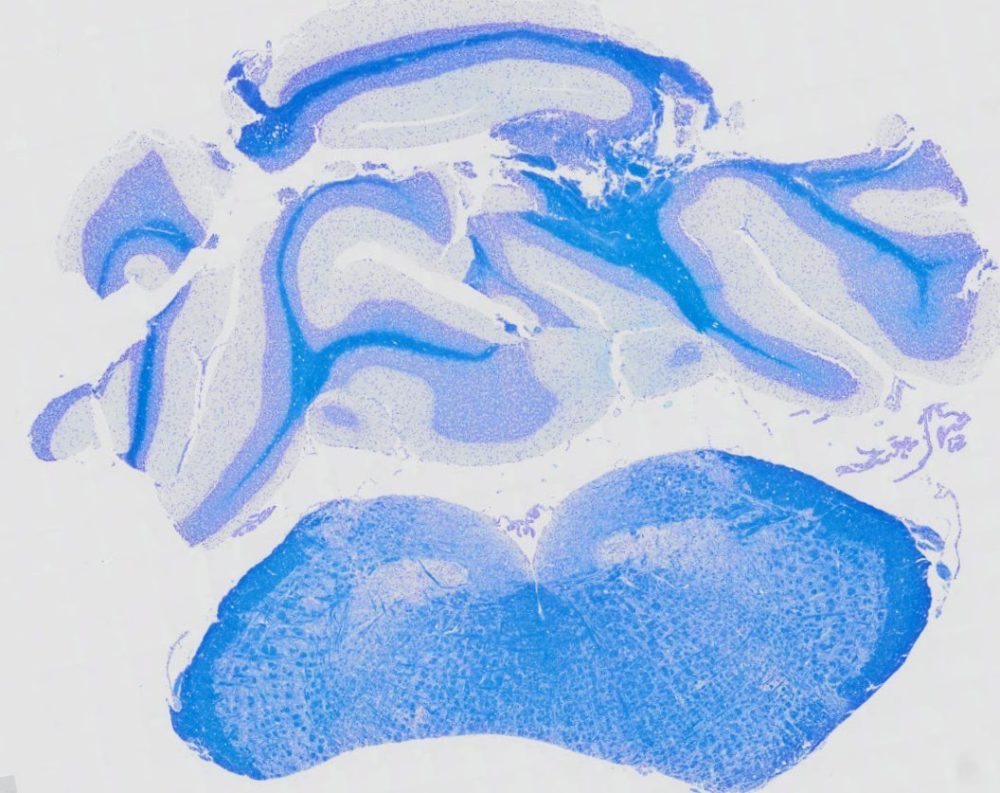

Luxol Fast Blue Stain Kit is designed for staining myelin/myelinated axons on formalin-fixed, paraffin-embedded brain and spinal cord tissue sections, as well as frozen sections. The myelin, including phospholipids, will be stained blue to green, and the neurons will be stained violet.This stain is commonly used for identifying the basic neuronal structure in brain or spinal cord tissue.

Results

- Myelin, including phospholipids —————-blue to green

- Neuron —————————————————-pink to violet

Positive Controls: Brain, spinal cord.